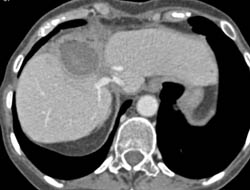

Liver Abscess